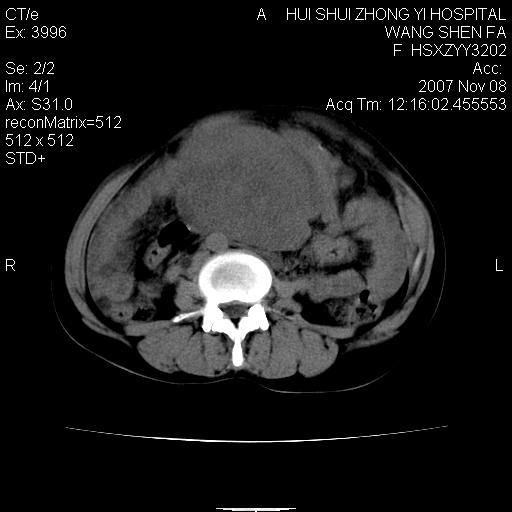

腹腔及盆腔内可见巨大软组织肿物影,内部密度欠均匀,边界尚清晰,周围组织受压移位明显,右侧输尿管受压明显,上端扩张肾盂轻度积水,病灶外形分叶明显,似多个肿物融合而成。考虑来源于间叶组织的恶性肿瘤可能性大

下腹部巨大软组织影,密度不均匀,并可见分隔,病灶边缘较清,肠管受压移位。子宫未显示。盆腔、双侧腹股沟未见明显肿大淋巴结。考虑:1.卵巢病变可能性大,囊腺癌>卵巢癌>囊腺瘤.2.多发性阔韧带子宫肌瘤待除外.

腹腔及盆腔内可见巨大软组织肿物影,内部密度欠均匀,边界尚清晰,周围组织受压移位明显,膀胱前上移位,右侧输尿管受压明显,上端扩张肾盂轻度积水。考虑:1卵巢病变可能性大,囊腺癌>卵巢癌>囊腺瘤.2 子宫病变,子宫肌瘤?

盆腔及下腹部多发肿块,密度不均,与子宫关系密切,周围肠管受压改变,盆腔内未见肿大淋巴结,考虑多发性巨大子宫肌瘤可能。直接手术吧!

膀胱向前明显的推压移位,子宫增大明显,肠管推压移位,未见明显的侵润;患者女性,育龄期,考虑多发子宫肌瘤可能性大